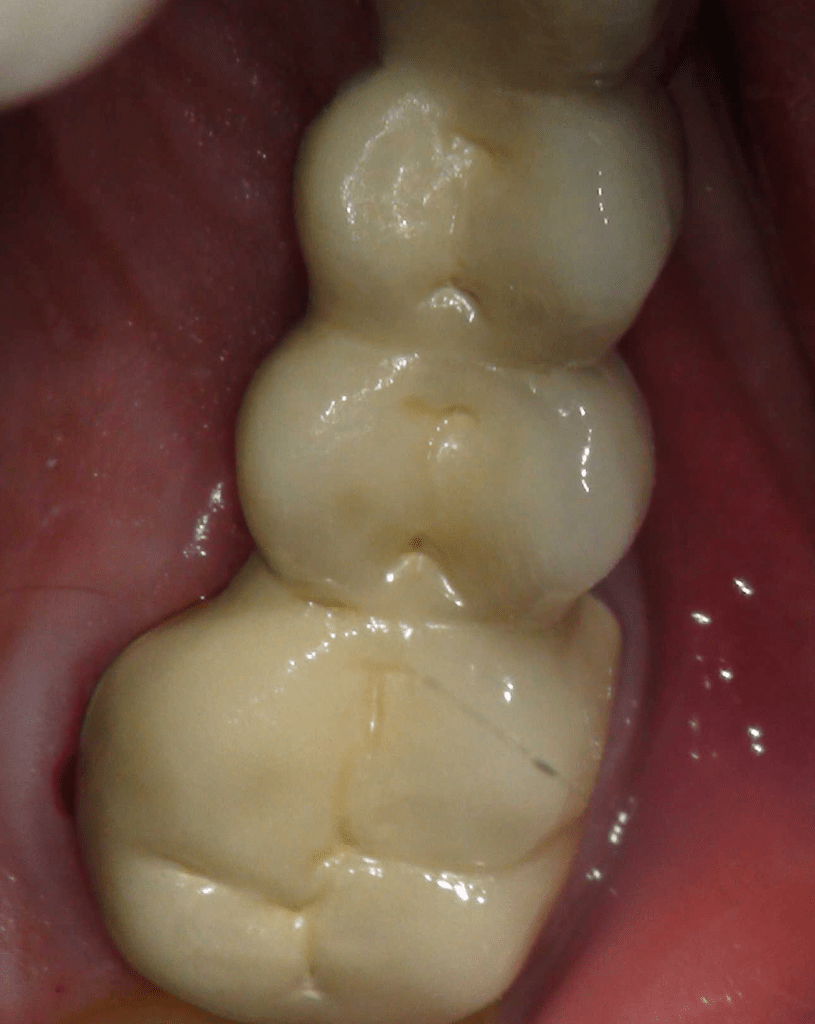

Diagnóstico de fisuras y fracturas

Fisura, remoción amalgama para explorar

Fractura cuspídea tratable